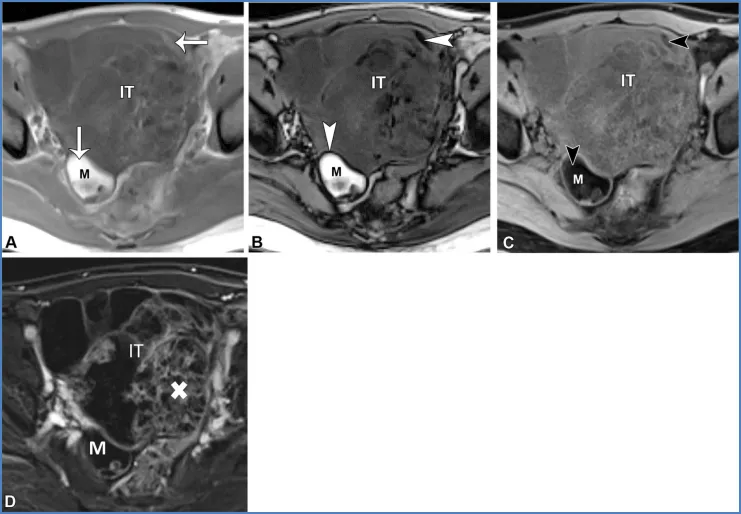

图19. 一名28岁女性患者的右侧成熟畸胎瘤和左侧未成熟畸胎瘤。这两个病灶都含有脂质,但成熟畸胎瘤(M)通常表现为充满脂质的囊肿,而未成熟畸胎瘤(IT)是复杂的多房囊性肿块,伴有强化的实性组织和散在的小脂质灶。肉眼可见的脂肪可通过以下特征识别:在轴位同相位T1加权图像上呈高信号(A中的箭头),在轴位反相位T1加权图像上的脂肪-水界面存在印度墨汁伪影(黑色边界伪影)(B中的箭头),以及在轴位脂肪抑制T1加权图像上信号被抑制(C中的箭头)。与成熟畸胎瘤可能在罗基坦斯基结节中显示强化不同,未成熟畸胎瘤在增强成像时显示大量强化的实性组织(白色X),如轴位减影图像(D)所示。

成熟畸胎瘤通常无症状,但可能会引起扭转相关的疼痛。它们通常表现为囊肿,主要含有肉眼可见的脂质、偶尔可见的镜下脂质、毛发、皮肤成分以及牙齿样钙化(在T1和T2加权像上呈低信号)。它们可能会有弥散受限,还可能包含强化的罗基坦斯基结节,但这些都不是恶性的迹象(图19)(19,57,60,61)。极少情况下,含脂质的病变可能是恶性的。在老年患者中,成熟畸胎瘤可能发生恶性转化(≤2%),通常会转化为鳞状细胞癌;一个关键的影像学特征是较大的实体组织,常伴有跨壁延伸(19,62)。30岁以下女性可能会出现未成熟畸胎瘤,这是一种恶性卵巢生殖细胞肿瘤,常伴有血清甲胎蛋白和乳酸脱氢酶水平升高。未成熟畸胎瘤表现为大型单侧囊性病变,伴有实体组织、散在的小脂质灶以及不规则的小钙化,这些在MRI上可能难以检测到(图19)(62,63)。